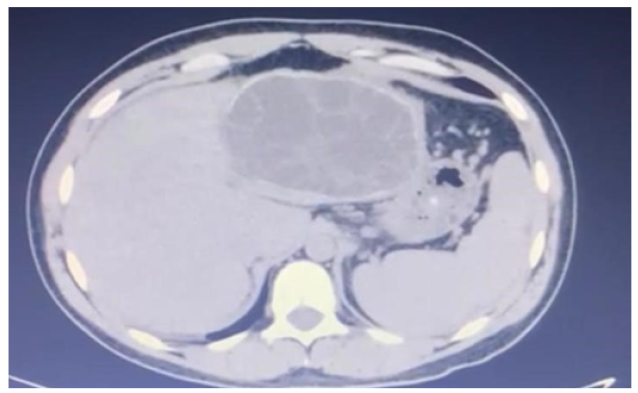

Successful Laparoscopic Management of Giant Hydatid Liver Cyst: A Case Report

Loai Saleh Albinsaad, Arshadullah Khan, Mohammed Yousef Alessa, Ali Abdulhamid Almohammed saleh and Abdulmohsen Yaseer Alkhars. 6(3): 19-24.